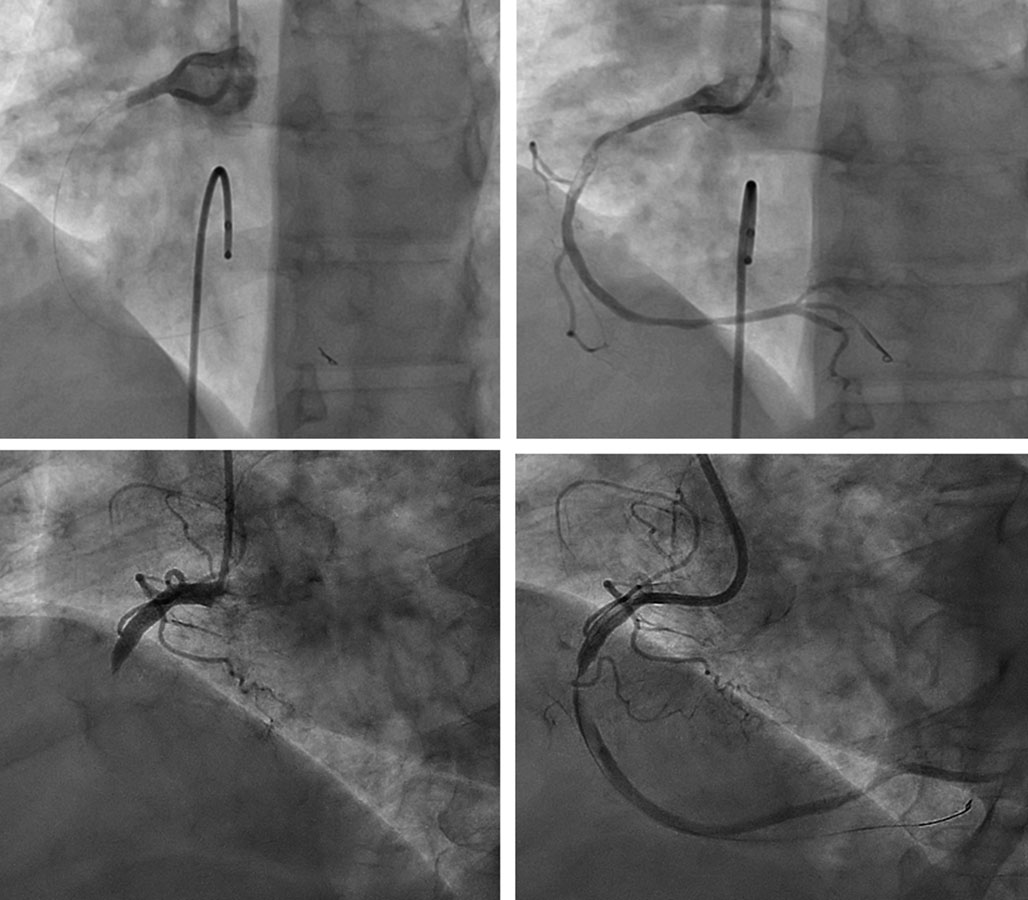

De toda la cohorte, 124 pacientes (95,4%) presentaron lesiones culpables con GCT. Previamente a la liberación de la energía láser, se informó de un grado de flujo TIMI 0 en 79 casos (60,8%) y TIMI 1 en 32 (24,6%). Tras la ELCA, se alcanzó un grado de flujo TIMI 2 y 3 en 45 (34,6%) y 66 (50,8%) casos, respectivamente; p < 0,001) (figura 1).

Figura 3. Hallazgos antes y tras la ELCA en 2 casos típicos de coronaria derecha con gran carga trombótica. ELCA: angioplastia coronaria con láser de excímeros.